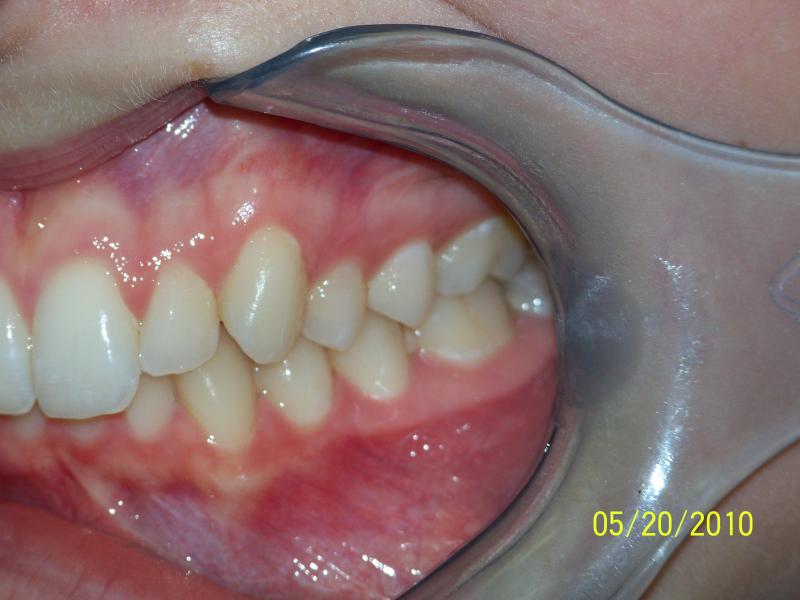

INVISALIGN, 10 months, 1 series of aligners to correct alignment, deep overbite and shift teeth to the right to match upper and lower mid line, TOTAL TREATMENT TIME: 10 months COSMETIC DENTISTRY: incisal reduction of anterior teeth before and after Invisalign.

Deep Overbite, Teeth Reshaping, Testimonial